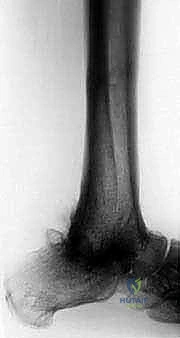

1. الأشعة السينية (X-rays): لتقييم مدى تدمير المفصل، وجود تشوهات، وفقدان العظم. يتم أخذ صور في وضعيات مختلفة (أمامية، جانبية، وأثناء الوقوف إن أمكن).

2. الأشعة المقطعية (CT Scan): ضرورية جداً للتخطيط الجراحي. توفر صوراً ثلاثية الأبعاد تُظهر بدقة كمية العظم المتبقي، جودة العظم، ومواقع التكيسات أو النخر العظمي.